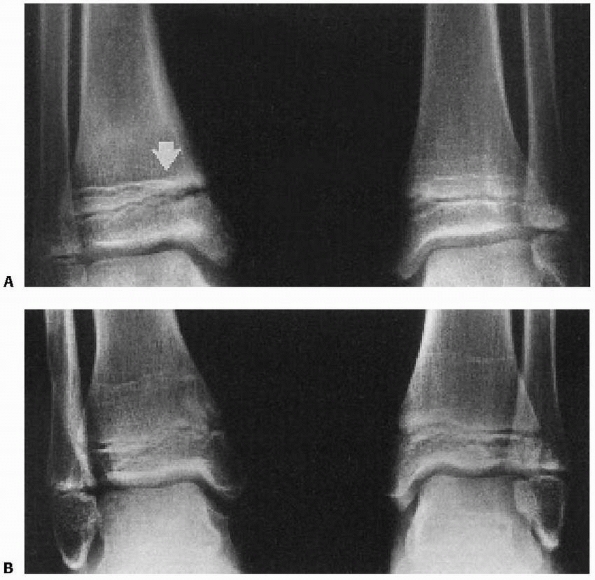

![]() |

FIGURE 26-39 A. Supination-inversion injury with a Salter-Harris type III fracture of the medial malleolus. B. Six months after open reduction and internal fixation with two transepiphyseal cannulated screws. C. Eighteen months after injury, the fracture has healed with no evidence of growth arrest or angular deformity. (Arrows note normal, symmetric Park-Harris growth arrest line.)

|

FIGURE 26-40 Compression-type injury of the tibial physis. Early physeal arrest can cause leg-length discrepancy.